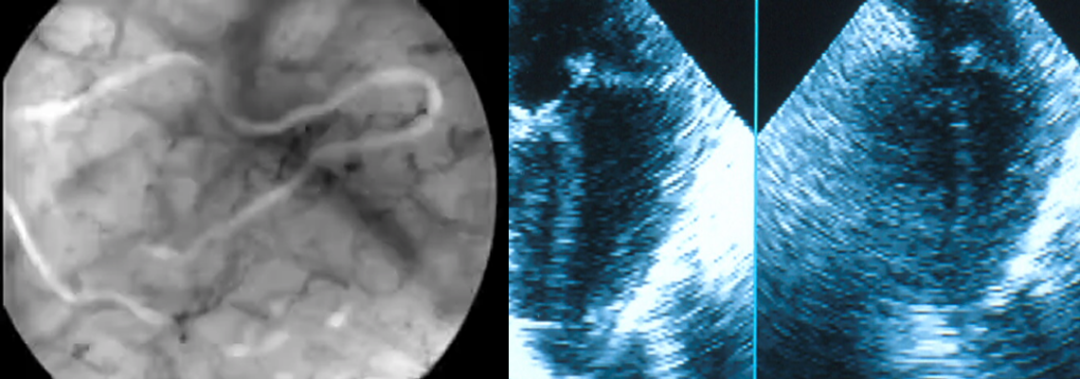

Dr Tang:In fact, chest compression is only a pathway, a bridge, the aim is, before eradicating causes of cardiac arrest, to provide temporary oxygenated blood flow to the body and maintain blood flow of vital organs through effective chest compression, keeping the organs to maintain in a condition of survival. Therefore, the aim of resuscitation should go back to the origin of the disease - rebuilding heart, coronary perfusion pressure and myocardial perfusion.

1.Should develop and applynon-invasive physiologic vascular study, monitor the change in blood circulation in real life, determine resuscitation strategy, for example, the newest non-invasive carotid monitoring system is a good start.

3.Rectify reversible cause and clogged coronary artery should be treated as soon as possible

We believe that when a healthy being loss conscious unexpectedly, it’s because of clogged coronary artery. If clogged artery could not be treated in short time, despite using ECMO to re-establish higher blood circulation, the heart muscle would still be under ischemic stage. Even if ROSC is achieved, it does not mean the last survival, the heart might arrest again anytime.

Actually not just Dr. Marko, lately in the Cardiac Arrest Center (CAC) constructing standard applied internationally and locally in China, requires an 24/7 PCI. Based on the research, it shows that 96% STEMI and 58% NSTEMI require emergency PCI. Treating the clogged artery will lead to a better recovery.

SunLife is developing PCI use Auto CPR Machine MCC-T, provide more technological support for emergency PCI.